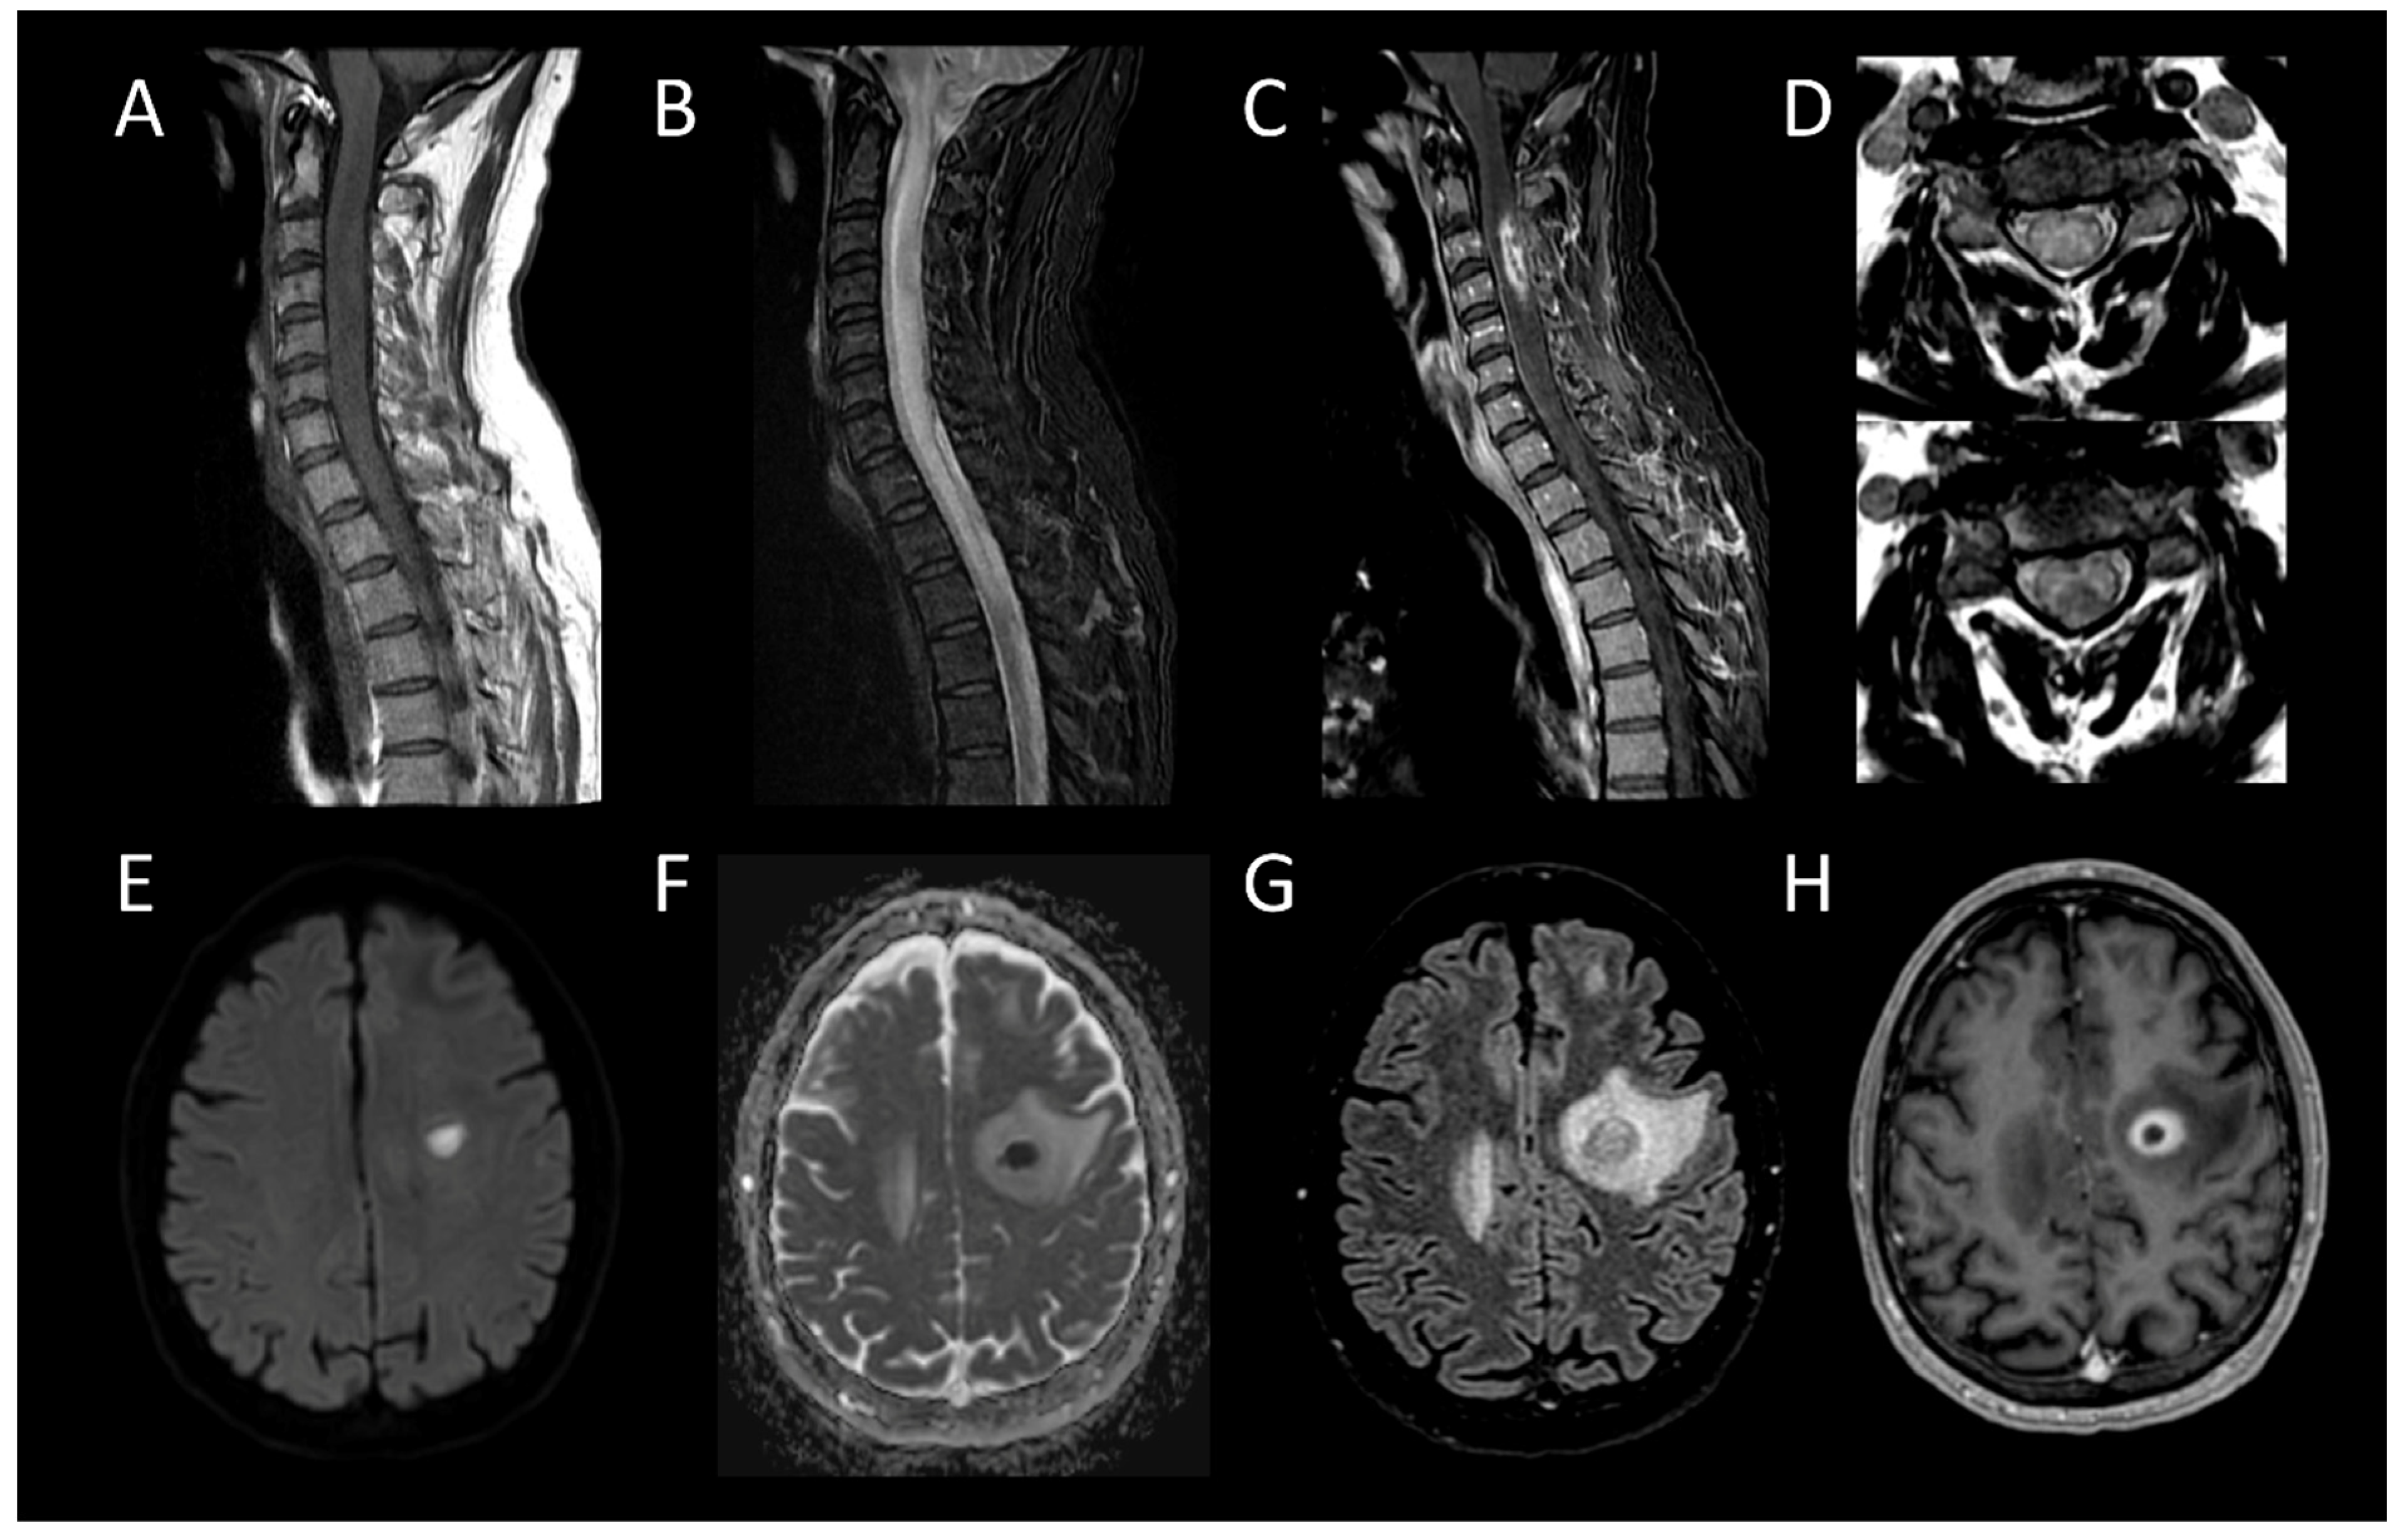

3.1. Inflammatory Myelitis

3.1.2. Longitudinally Extensive Myelitis

Neuromyelitis Optica Spectrum Disorders Positive for Aquaporin-4 IgG

Myelin-Oligodendrocyte Glycoprotein Antibody Associated Disease

Neurosarcoidosis

3.3.1. Spinal Cord Infarction